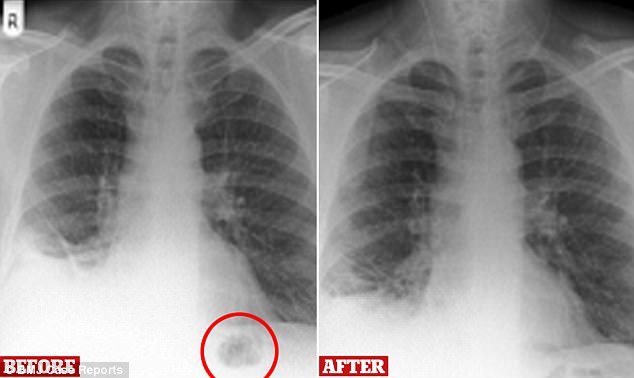

엑스레이 정밀검사 결과, 그의 페에 거대한 덩어리가 나타났고, 전문의는 남성이 30년째 흡연을 해왔음을 근거로 폐암 혹은 기관지암의 증상일 수 있다고 추정했다.

그러나 그의 기도를 검사하는 동안 의료진들은 그 큰 덩어리의 정체가 종양이 아닌, 남성이 7살 때 삼킨 블록 장난감의 일부라는 사실을 발견했다.

남성은 “자라면서 생일 선물로 특정 플레이모빌 세트를 받은 걸 기억한다. 자주 가지고 놀았고 실수로 삼키기도 했었던 것 같다”며 “작은 원뿔모양의 장난감을 없애고 4개월이 지나니 증상이 완화됐다”고 말했다.